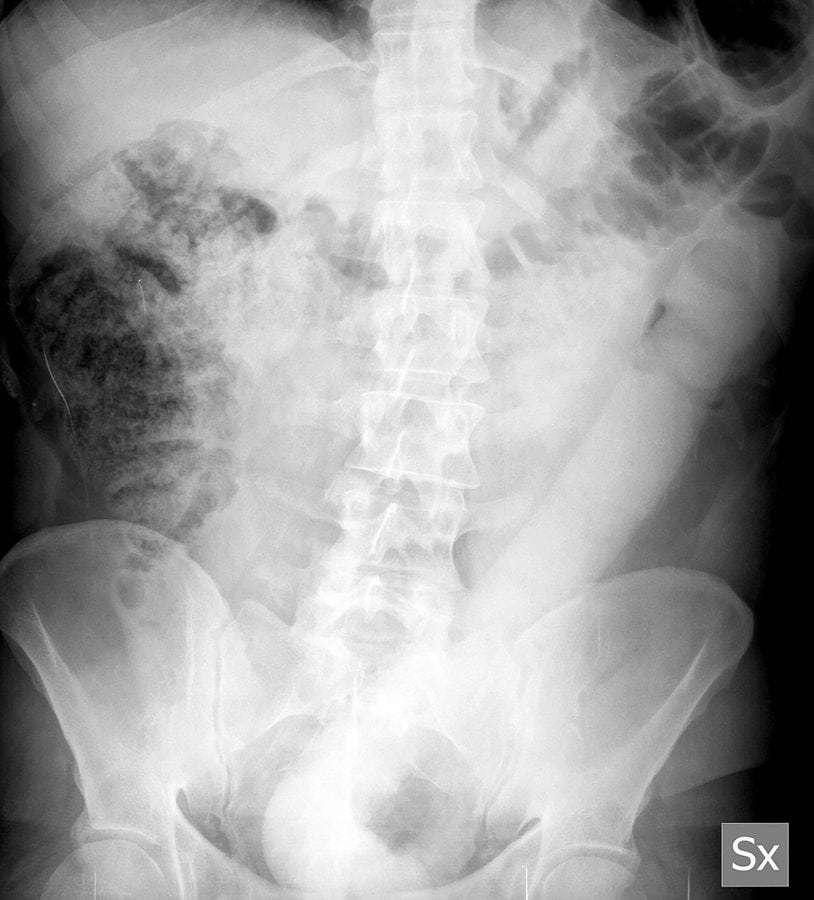

Annak ellenére, hogy ez félig-meddig hétköznapi gyakorlatnak számít, egy olasz úrnak sikerült meglepnie a milánói orvosokat: egy hatvancentis műfasz ragadt bele. A pasi azután kereste fel a kórházat, hogy már egy teljes napja a seggében hordozta ezt a szörnyeteget. Az orvosok nemrég adták közre, hogy hogyan sikerült segíteni a páciensen, ugyanis ehhez fel kellett találniuk egy új eszközt, amivel megoldhatták a problémát, így a történet ismeretlen hőse voltaképpen a tudomány haladásáért szenvedett – ezek után igazán elnevezhették volna róla a hurkot.